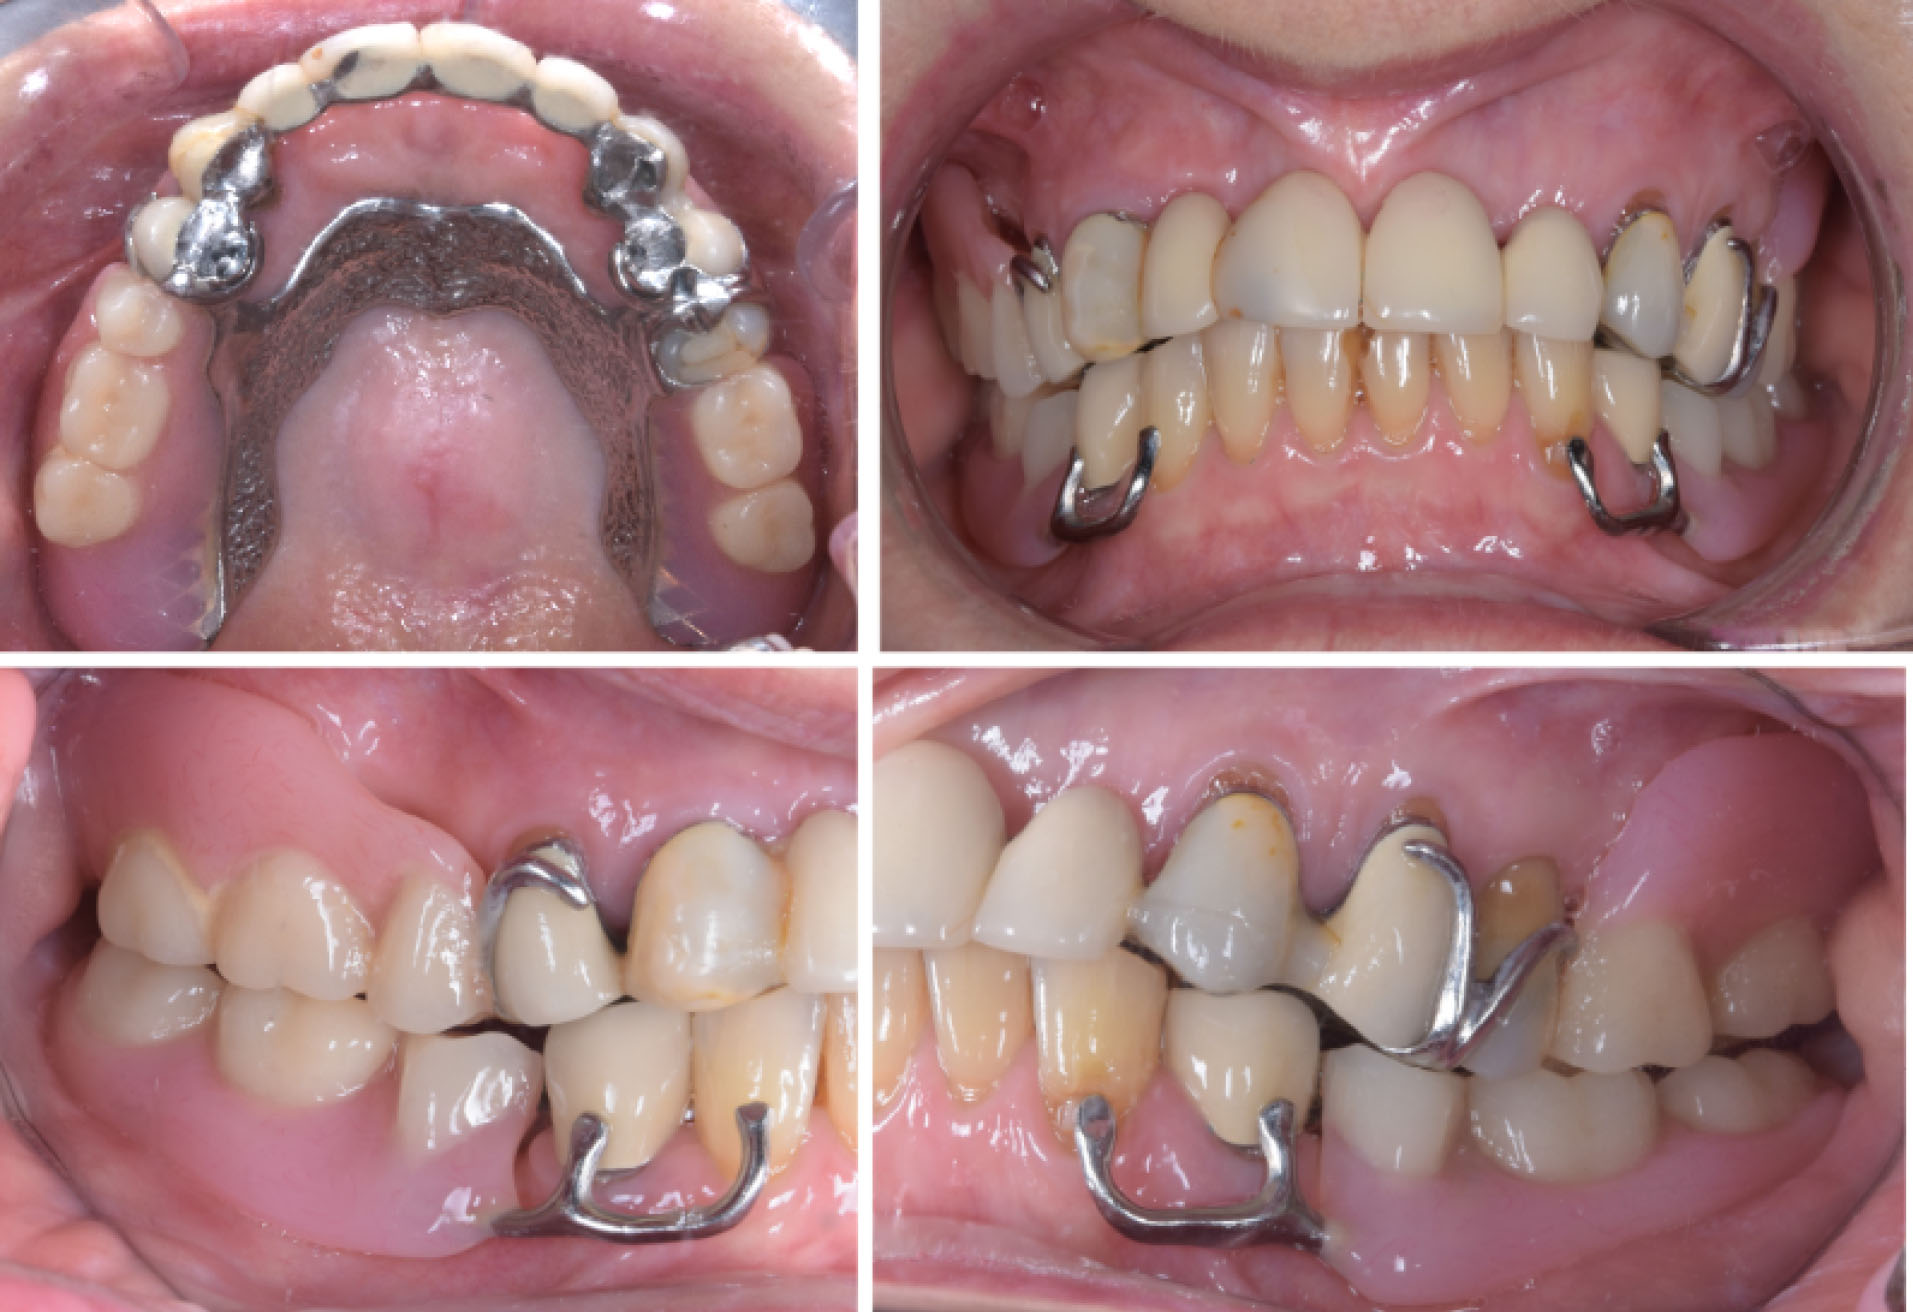

A 79-year-old Caucasian woman in good systemic health presented to the clinic reporting “sore gums” in the maxillary right canine region. After a thorough clinical examination, radiographs, diagnostic casts, and diagnostic articulator mounting, the tooth 13 was given hopeless prognosis as an abutment tooth required to support the anterior maxillary ceramic fixed dental prosthesis (). The same abutment tooth was involved in supporting a Kennedy class I removable partial denture. Considering the loss of strategic teeth and the patient’s desire of having fixed prostheses, extraction of all maxillary teeth followed by the placement of six implants using a computer-guided surgical approach to support a screw-retained full-arch ceramic prosthesis was planned. In the mandible, the patient was wearing an unsatisfactory Kennedy class I removable partial denture with poor retention and uneven occlusal plane. The curve of Spee was inverted at premolar area with overeruption of maxillary premolars, especially on the left-hand side. The mandibular first premolars had grade II mobility and horizontal bone loss, whereas the anterior teeth were vital with only minor incisal wear. Mandibular implant-supported fixed partial dentures were included in the treatment plan to replace the existing removable partial denture.

joddd-15-115-g001

Figure 1. Presenting condition of the patient. Long span metal-ceramic bridge replacing all missing anterior maxillary incisors and supported by canines and first premolars. Cobalt-chrome removable partial denture replacing missing posterior maxillary and mandibular teeth.